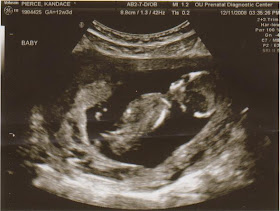

I meant to post this yesterday, but I was too tired! Yesterday was my first trimester screening for some of the more common chromosomal abnormalities (also known as the Nuchal Translucency--or NT--test). After waiting in the waiting room for about an hour, they finally called me back and first did genetic counseling to find out my family history. Blah blah, after the end of that, he said I have about a 1:1000 chance of Down's Syndrome. Then on to the ultrasound (my favorite part!) where they measure some fluid at the back of the baby's neck. That was also very normal. Then the lovely technician took took several pictures of baby, and we got to see her moving around and stretching and everything! She is getting sooo big! Here are some of the pics:

^This one is a profile view, head on the right

^This one is a close up of the side of her face (see the nose and lips?)

^This one is a close up of the side of her face (see the nose and lips?)

^This is the front of her face looking right at you

^And this is where she was stretching out